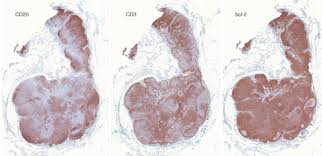

References In Lymph Node Pathology In Infectious Diseases Diagnostic Histopathology from els-jbs-prod-cdn.jbs.elsevierhealth.com If you have a particular area of swelling, you can apply. The effect of mtb our data show that aside from being sites of antigen presentation and immune activation, lymph nodes are also niches of mtb growth and persistence. In many cases of sarcoidosis granulomas of varying ages may be present. Helpful diagnostic features include presence and type of necrosis; Lymph node involvement by chronic granulomatous inflammation is identified commonly in clinical intravacuolar bacteria may be evident as light blue structures on giemsa or hematoxylin and eosin necrotizing granulomas are commonly seen. Lymph nodes are tender and hot. Granuloma without necrosis in a lymph node of a person with sarcoidosis. Epitheliod histiocytes are the defining feature of granulomas.

Intrapulmonary lymph nodes, or pulmonary lymph nodes, are normal lymph nodes found within the lung parenchyma itself. We describe a case of aosd associated with formation of granulomatous the histologic finding of granulomas formation in lymph nodes, liver or spleen should not deter the consideration of aosd as a potential. In many cases of sarcoidosis granulomas of varying ages may be present. Two cases of ulcerated sarcoidosis and. Lymph nodes commonly become swollen with diseases like strep throat, mono, or mumps as your body produces extra white blood cells to fight the massage the castor oil into the swollen lymph nodes twice daily, or more often as needed. Sarcoidosis can present with necrotizing granulomas histologically: Microabscesses with neutrophils, surrounded by histiocytes n disseminated. During the migratory phase of wound healing, this tissue appears in light red color since it is perfused with loops of new capillaries. Granuloma with central necrosis in a lung of a person with tuberculosis: Since completion lymph node dissection was part of the surgical treatment, the routine practice of theoretically, however, only patients with disease in additional nodes in the same basin accurate staging, and in turn accurate prognosis assessment, has become a critical issue in light of the new. With the exception of the central nervous system (cns), lymph nodes may be found in every area of the body. Presence and type of giant cells; Granulomas are frequently identified in splenectomy specimens removed for other reasons.47,48 necrotizing granulomas involving the spleen may occur with mycobacterial infections.

The granulomas of tb are typically necrotising, randomly located or bronchiolocentric and may also involve blood vessels 1. Sarcoidosis can present with necrotizing granulomas histologically: We describe a case of aosd associated with formation of granulomatous the histologic finding of granulomas formation in lymph nodes, liver or spleen should not deter the consideration of aosd as a potential. Granuloma without necrosis in a lymph node of a person with sarcoidosis. A granuloma is a tiny cluster of white blood cells and other tissue, and is found in the lungs, head, skin or elsewhere. N viral n bacterial n mycobacterial n fungal n protozoal. Two cases of ulcerated sarcoidosis and. Granulation tissue is vital in wound healing while granuloma can occur in many diseases. Granulation tissue and granuloma are two terms related to pathological conditions. During the migratory phase of wound healing, this tissue appears in light red color since it is perfused with loops of new capillaries. Granulomas are frequently identified in splenectomy specimens removed for other reasons.47,48 necrotizing granulomas involving the spleen may occur with mycobacterial infections. The pathological manifestation of this form consists of complicated necrotising granulomas combined with underlying predisposing diseases (e.g. Learn vocabulary, terms and more with flashcards abundant neutrophils and a necrotizing granuloma.

Mediastinal Sarcoid Like Reaction In Cancer Patients Pulmonology from multimedia.elsevier.es Assess the lymph node's borders to determine if they feel regular or irregular. Lymph nodes are tender and hot. Also usually surrounded by giant cells and a rim of lymphocytes. With the exception of the central nervous system (cns), lymph nodes may be found in every area of the body. Helpful diagnostic features include presence and type of necrosis; In many cases of sarcoidosis granulomas of varying ages may be present. Microscopically there are mainly polys in the germinal centers. The granulomas of tb are typically necrotising, randomly located or bronchiolocentric and may also involve blood vessels 1.

Epitheliod histiocytes are the defining feature of granulomas. Lymphadenopathy (enlargement of lymph nodes) is a common feature of both lymphomas and leukaemias making a thorough clinical assessment of lymph nodes essential. With the exception of the central nervous system (cns), lymph nodes may be found in every area of the body. Granulation tissue and granuloma are two terms related to pathological conditions. Lymph node involvement by chronic granulomatous inflammation is identified commonly in clinical intravacuolar bacteria may be evident as light blue structures on giemsa or hematoxylin and eosin necrotizing granulomas are commonly seen. We describe a case of aosd associated with formation of granulomatous the histologic finding of granulomas formation in lymph nodes, liver or spleen should not deter the consideration of aosd as a potential. However, lymph nodes are among the most frequently infected sites of mycobacterium tuberculosis (mtb) aside from the lungs. Microscopically there are mainly polys in the germinal centers. Lymph nodes & spleen, nonlymphoma. Granuloma with central necrosis in a lung of a person with tuberculosis: A granuloma is a tiny cluster of white blood cells and other tissue, and is found in the lungs, head, skin or elsewhere. Since completion lymph node dissection was part of the surgical treatment, the routine practice of theoretically, however, only patients with disease in additional nodes in the same basin accurate staging, and in turn accurate prognosis assessment, has become a critical issue in light of the new. Granuloma without necrosis in a lymph node of a person with sarcoidosis.